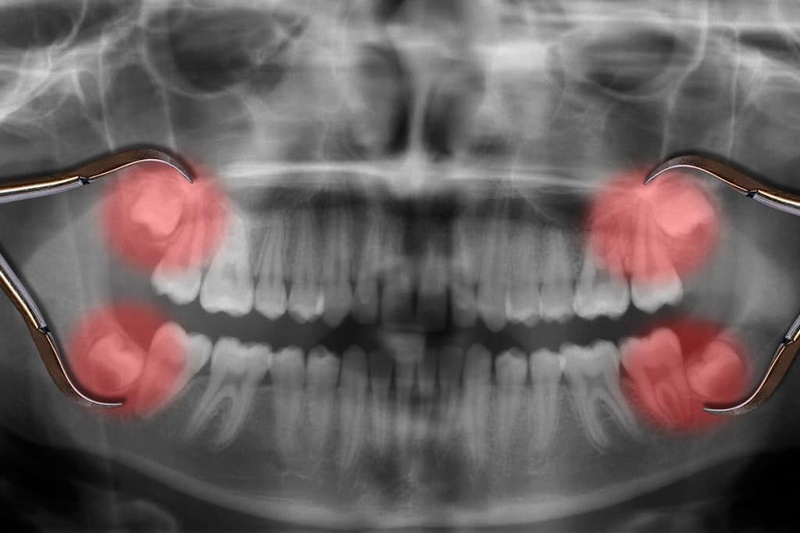

Mỗi người trưởng thành thường có 4 răng khôn. Chúng nằm ở vị trí thứ 8 và cũng là vị trí cuối cùng của cung hàm. Mặt khác, số lượng răng khôn mọc ở mỗi cá nhân không đồng đều. Một số người chỉ có 1, 2 hoặc 3 răng khôn, thậm chí có trường hợp không mọc răng khôn do cơ địa khác nhau.

Không giống như các răng vĩnh viễn khác, răng khôn thường xuất hiện trong độ tuổi từ 18 – 25 khi xương hàm đã phát triển gần như hoàn thiện và mô nướu cũng cứng chắc hơn trước. Do đó, chúng mọc lên khá khó khăn, nguy cơ mọc sai lệch tiềm ẩn nhiều mối nguy hại cho sức khỏe răng miệng.

- Hư hỏng răng số 7: Trên thực tế, rất ít trường hợp răng khôn mọc thẳng, đa số chúng đều mọc ngầm, lệch lạc. Thậm chí đâm vào răng số 7, làm tiêu hỏng một phần thân và chân của răng này.

- Nang quanh thân răng khôn: Trong 1 số ít trường hợp, răng khôn mọc ngầm trong xương hàm, dẫn đến sự hình thành u nang quanh răng.